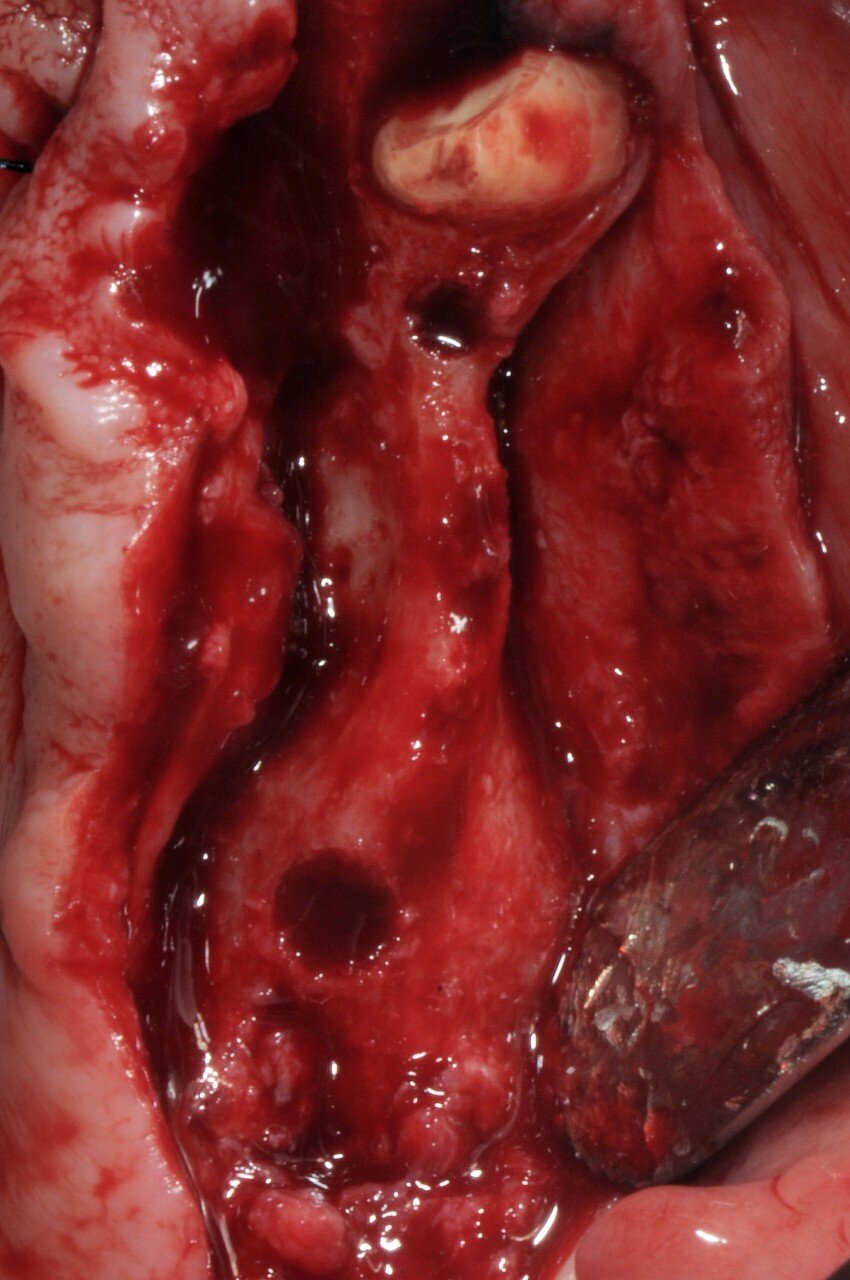

È stato eseguito un lembo a spessore totale senza tagli verticali di rilascio e una regolarizzazione della cresta ossea per mezzo di un raschietto per osso, che ha permesso di ottenere una quantità ulteriore di osso oltre a quello ottenuto per mezzo della fresatura a basso numero di giri secondo la procedura BTI. L’osso ottenuto è stato mischiato con gel piastrinico ottenuto mediante centrifugazione del sangue del paziente secondo la metodica PRGF Endoret ed inserito in parte all’interno dell’osteotomia del dente 26 a protezione della membrana sinusale e in parte protezione della parete ossea vestibolare del dente 24 che era particolarmente sottile. Dopo aver applicato i tappi di guarigione i lembi sono stati suturati per ottenere una guarigione sommersa (Figg. 5-7). Dopo quattro mesi di guarigione gli impianti furono scoperti e due pilastri Multi-im sono stati avvitati con i relativi tappi di guarigione.